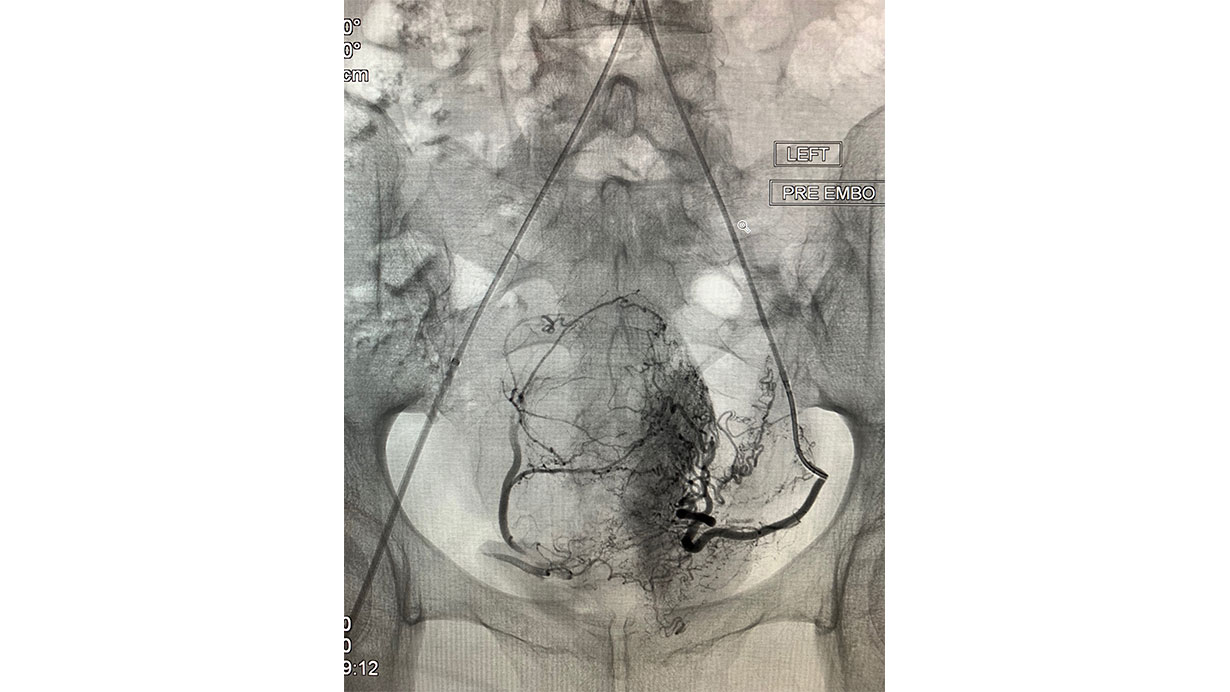

UFE Angiography

During this procedure, your IR shrinks your fibroids by blocking off their blood supply. Using a catheter (a slender tube) that is directed into the arteries of the pelvis using x-ray imaging, tiny particles (smaller than the size of a grain of sand) are injected directly into the arteries that supply your fibroids. These particles selectively block the feeding blood supply of the fibroid, causing them to shrink over time, reducing or resolving most symptoms.